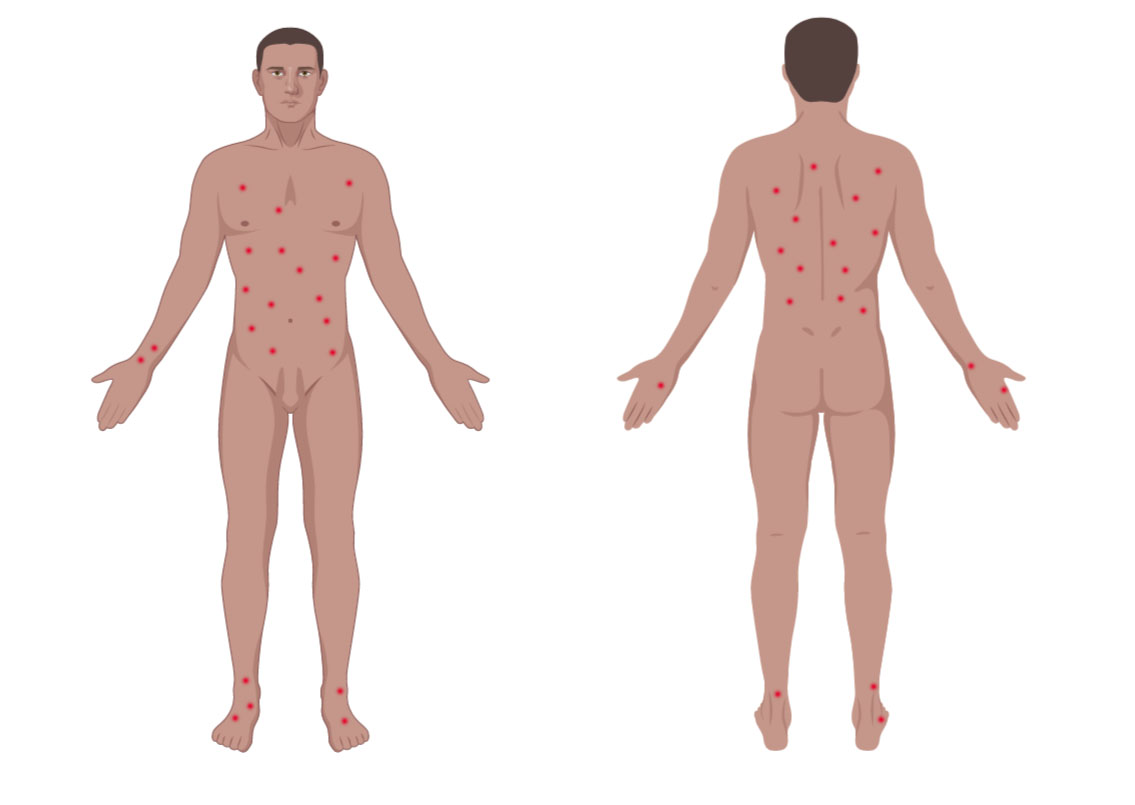

- More common in trunk and extremities but can affect any body part (J Am Acad Dermatol 2016;74:59, Am J Clin Dermatol 2016;17:319)

- Single or clustered red or purple papules and small nodules (< 2.0 cm) with different stages of development; spontaneous regression in few weeks and indolent clinical course (Hematol Oncol 2019;37 Suppl 1:43, J Am Acad Dermatol 2016;74:59, Arch Dermatol 2009;145:966, Semin Diagn Pathol 2017;34:22, Clin Exp Dermatol 2018;43:137)

- More common in trunk and extremities but can affect any body part (J Am Acad Dermatol 2016;74:59, Am J Clin Dermatol 2016;17:319)

- Clusters of red or purple papules and small nodules (< 2.0 cm each) with different stages of development, spontaneous regression in few weeks and indolent clinical course (Hematol Oncol 2019;37 Suppl 1:43, J Am Acad Dermatol 2016;74:59, Arch Dermatol 2009;145:966, Semin Diagn Pathol 2017;34:22, Clin Exp Dermatol 2018;43:137)

- Less commonly, single or multiple crops; the disease can persist from several weeks to years (J Am Acad Dermatol 2016;74:59, Semin Diagn Pathol 2017;34:22, Clin Exp Dermatol 2018;43:137)

- The severity of lesions is defined as: mild (< 12 lesions), moderate (12 - 50 lesions) and severe (> 50 lesions) (J Am Acad Dermatol 2016;74:59)